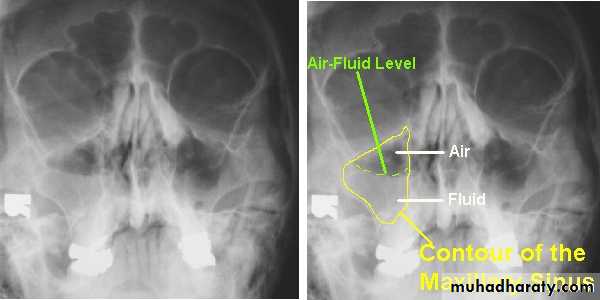

SINUSITIS:Infection of sinus

S/S:

Headache

Thick purulent discharge from nose

DRAINING MAXILLARY SINUS:

Frontal sinusitis and ethamoidal sinusitis can cause edema of the lids secondary to infection of the sinusesRADIOGRAPHIC FINDINGS:

DIAGNOSIS:X-ray PNS.

CT Scan of PNS ( Coronal & Axial).